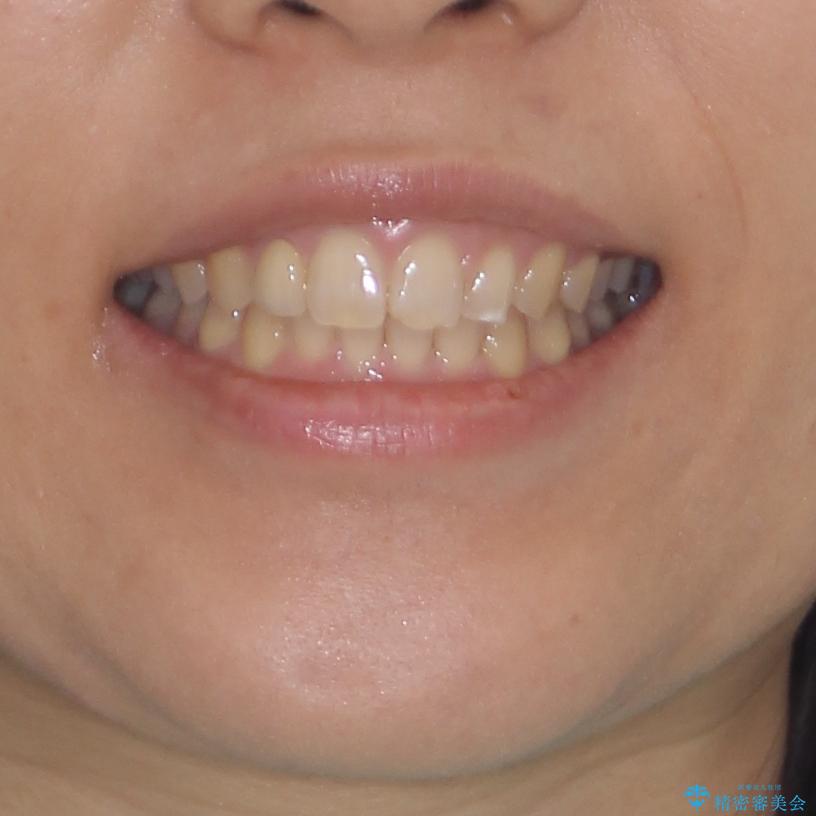

前歯の歯並びと小さい歯を改善 インビザラインとオールセラミッククラウン

- 前歯の空隙と矮小歯を気にして来院された患者様です。

上下の歯列不正はインビザラインにより整えることとしました。

矯正治療の後に、前歯1歯と奥歯をオールセラミックにて治療することとしました。

矯正治療により矮小歯前後にスペースを作りながら歯列を整え、セラミッククラウン装着後に最終的に歯列と咬合を仕上げました。